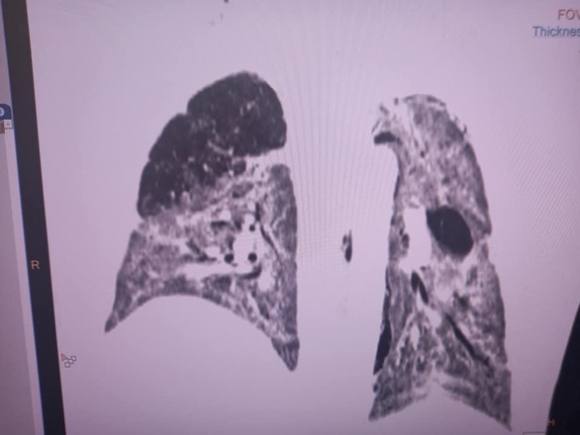

Nhưng thật lòng tôi thấy anh khó qua khỏi. Xét nghiệm thì thấy các chỉ số của bão cytokine đang hoành hành dữ dội. Hai lá phổi viêm trắng xóa, thở vào đâu? Chúng tôi phải dùng tối đa oxy hỗ trợ: thở oxy dòng cao HFNC 60 lít/phút, rồi lại chụp thêm ra ngoài một cái mask oxy 15 lít phút.

Lá phổi trên phim CT 1 ngày trước, chỉ một chút phổi lành màu đen, bên phải, nhưng đã khá hơn trước - Ảnh: Bệnh viện cung cấp

Buổi chiều, theo chỉ đạo của trưởng khoa, chúng tôi đẩy anh đi chụp cắt lớp CT phổi. Nhìn phổi của anh đông đặc gần hết, chỉ còn một chút phổi lành, thế mà anh cai oxy dòng cao được. Thật là kỳ diệu. Lòng quyết tâm của người làm cha đã làm nên điều kỳ diệu này chăng?